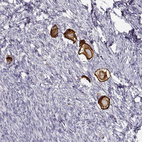

Immunohistochemical staining of human ovary shows strong membranous and cytoplasmic positivity in oocyte.